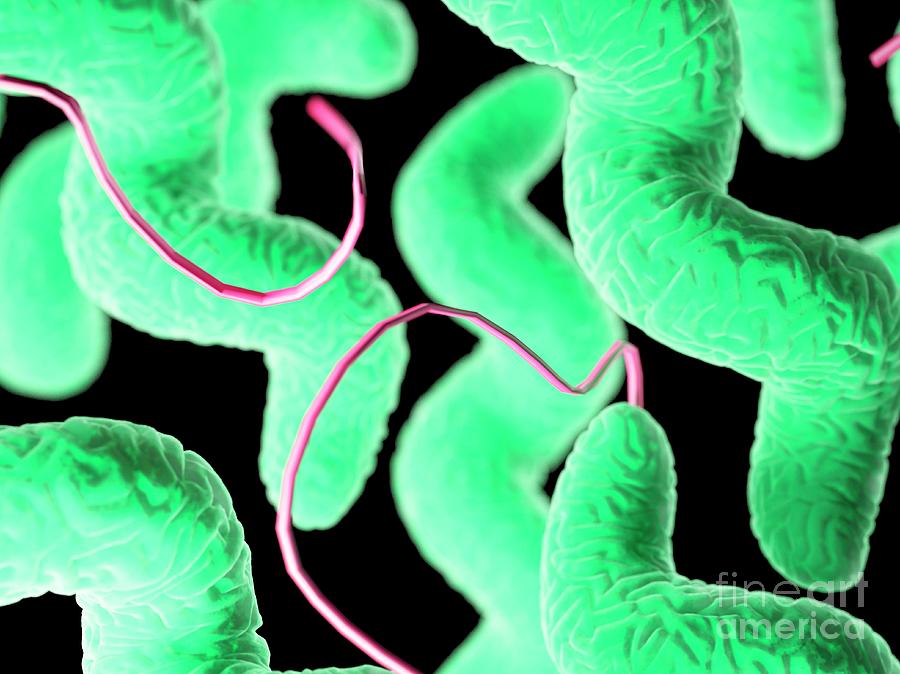

Кампилобактер фетус: патогенез и инфекции